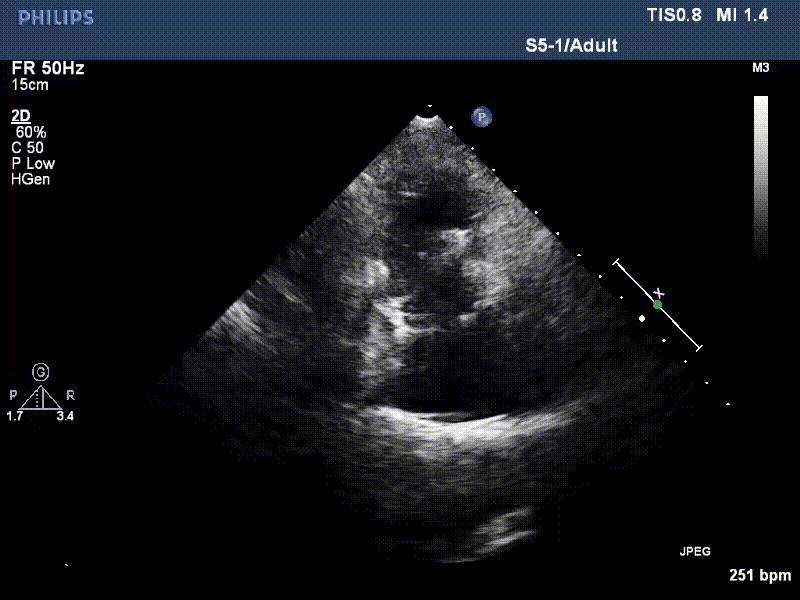

LuX-Valve Plus早期救治性臨床研究入組的首兩例患者均接受過二尖瓣人工瓣膜置換手術(shù),術(shù)前NYHA心功能均為Ⅲ級,極重度三尖瓣反

流并分別伴有房顫和房撲,高外科手術(shù)風(fēng)險。術(shù)前超聲提示,兩例患者下腔靜脈寬度分別為13mm和29mm,右房內(nèi)徑(上下徑和左右徑)分別為52×41mm和53×43mm,彩色多普勒顯示極重度三尖瓣反流,VCW分別為14×15mm和10mm。

1年前,兩例患者因難治性雙下肢水腫輾轉(zhuǎn)多家醫(yī)院尋求救治,考慮到兩例患者高齡、基礎(chǔ)疾病多、STS評分高,不適合傳統(tǒng)外科開胸手術(shù),葛均波院士及其團(tuán)隊周達(dá)新教授、潘文志教授、張源博士、陳莎莎博士、陳丹丹博士聯(lián)合心外科王春生、魏來主任,麻醉科繆長虹、郭克芳主任以及心超室的潘翠珍教授、李偉教授共同討論決定,采用我國創(chuàng)新器械LuX-Valve Plus經(jīng)血管三尖瓣置換系統(tǒng)為患者進(jìn)行手術(shù)。相較于第一代產(chǎn)品LuX-Valve,LuX-Valve Plus經(jīng)血管三尖瓣置換系統(tǒng)對輸送系統(tǒng)進(jìn)行了全面升級,實現(xiàn)了經(jīng)頸靜脈入路的方式,進(jìn)一步減小了手術(shù)風(fēng)險和對患者的創(chuàng)傷。目前隨訪1年心超結(jié)果顯示,三尖瓣極重度反流消失,人工三尖瓣瓣膜穩(wěn)定牢固,瓣葉活動度良好,右心室及下腔靜脈明顯縮小,心輸出量增加。兩位老人手術(shù)后沒有出現(xiàn)過胸悶氣促的癥狀,下肢水腫緩解,活動耐力提升,生活質(zhì)量也大為提高。

圖2 患者植入LuX-Valve Plus后,1年隨訪心超提示無三尖瓣反流